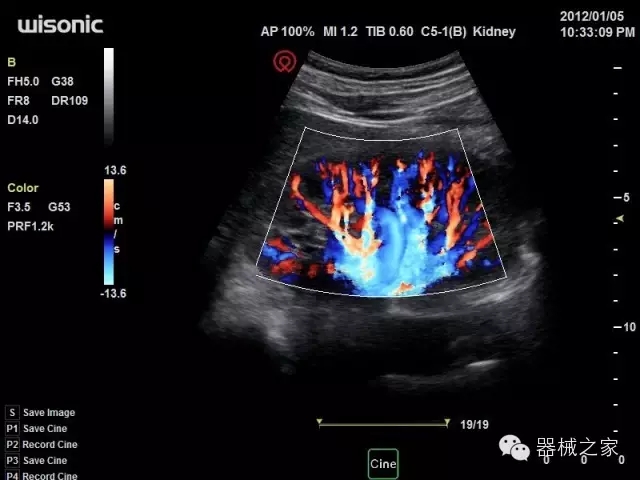

臨床圖片賞析

產(chǎn)品特點

·一款互聯(lián)網(wǎng)彩超,只要有手機(jī)信號的地方就可以非常方便地實現(xiàn)遠(yuǎn)程會診和病案調(diào)??;

·WIFI、網(wǎng)口、3G,多重聯(lián)網(wǎng)方式,全天候保障云端備份,不再擔(dān)心圖像丟失;